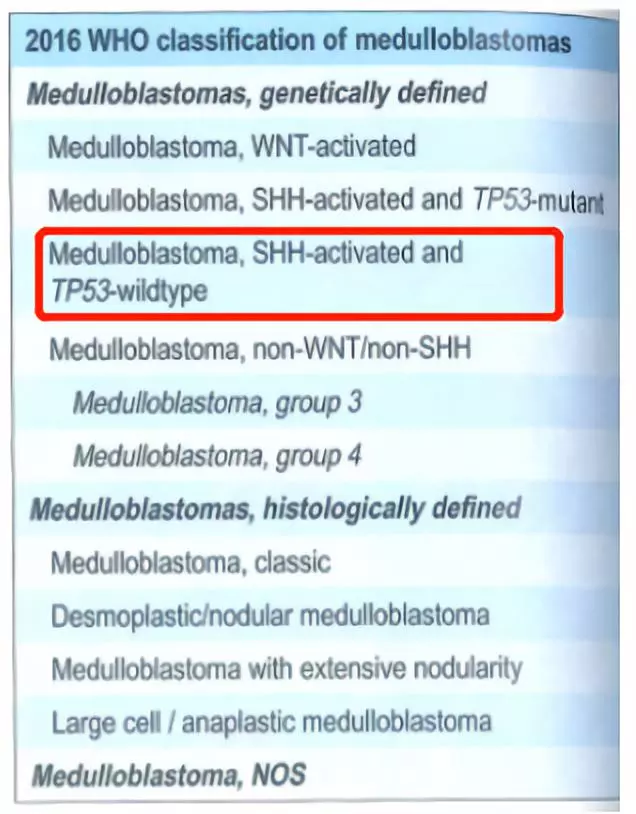

结合WHO中枢神经系统肿瘤分类指南(2016),基因检测结果显示:患者属于髓母细胞瘤, SHH激活及TP53野生型(图3、图4、图5)。分子评估其危险等级倾向于标危,需结合临床共同判断文献报道预后的5年中位总生存率为76%,但有APC遗传可能有其他肿瘤发生的风险。

图5. WHO中枢神经系统肿瘤分类指南(2016)

2016年新版 WHO中枢神经系统肿瘤分类指南,联合组织学表型和分子分型,重新规划了髓母细胞瘤的分类。该分类不仅包含了临床应用已久的组织学分型(如促纤维组织增生型/结节型、广泛结节型、大细胞型和间变型),还包含了现今被广泛接受的4种基因分型:WNT激活型、SHH激活型、Group3和Group4。这些不同的组织学分型和基因分型在预后和治疗上存在显著差异,其中SHH激活型在4种髓母细胞瘤基因分型中发病率占第2位,约为30%,发病人群多见于婴儿(<4岁)或大多数成人(>16岁),预后较WNT激活型差。这部分患者属于标危,目前术后治疗方式倾向于进行常规放化疗即可。但是部分SHH型患者伴有TP53突变,属于极高危,预后极差,术后常规化疗基础上还可联合干细胞治疗。本病例属于SHH激活型,但TP53未突变,结合临床情况选择了标危的治疗方案。